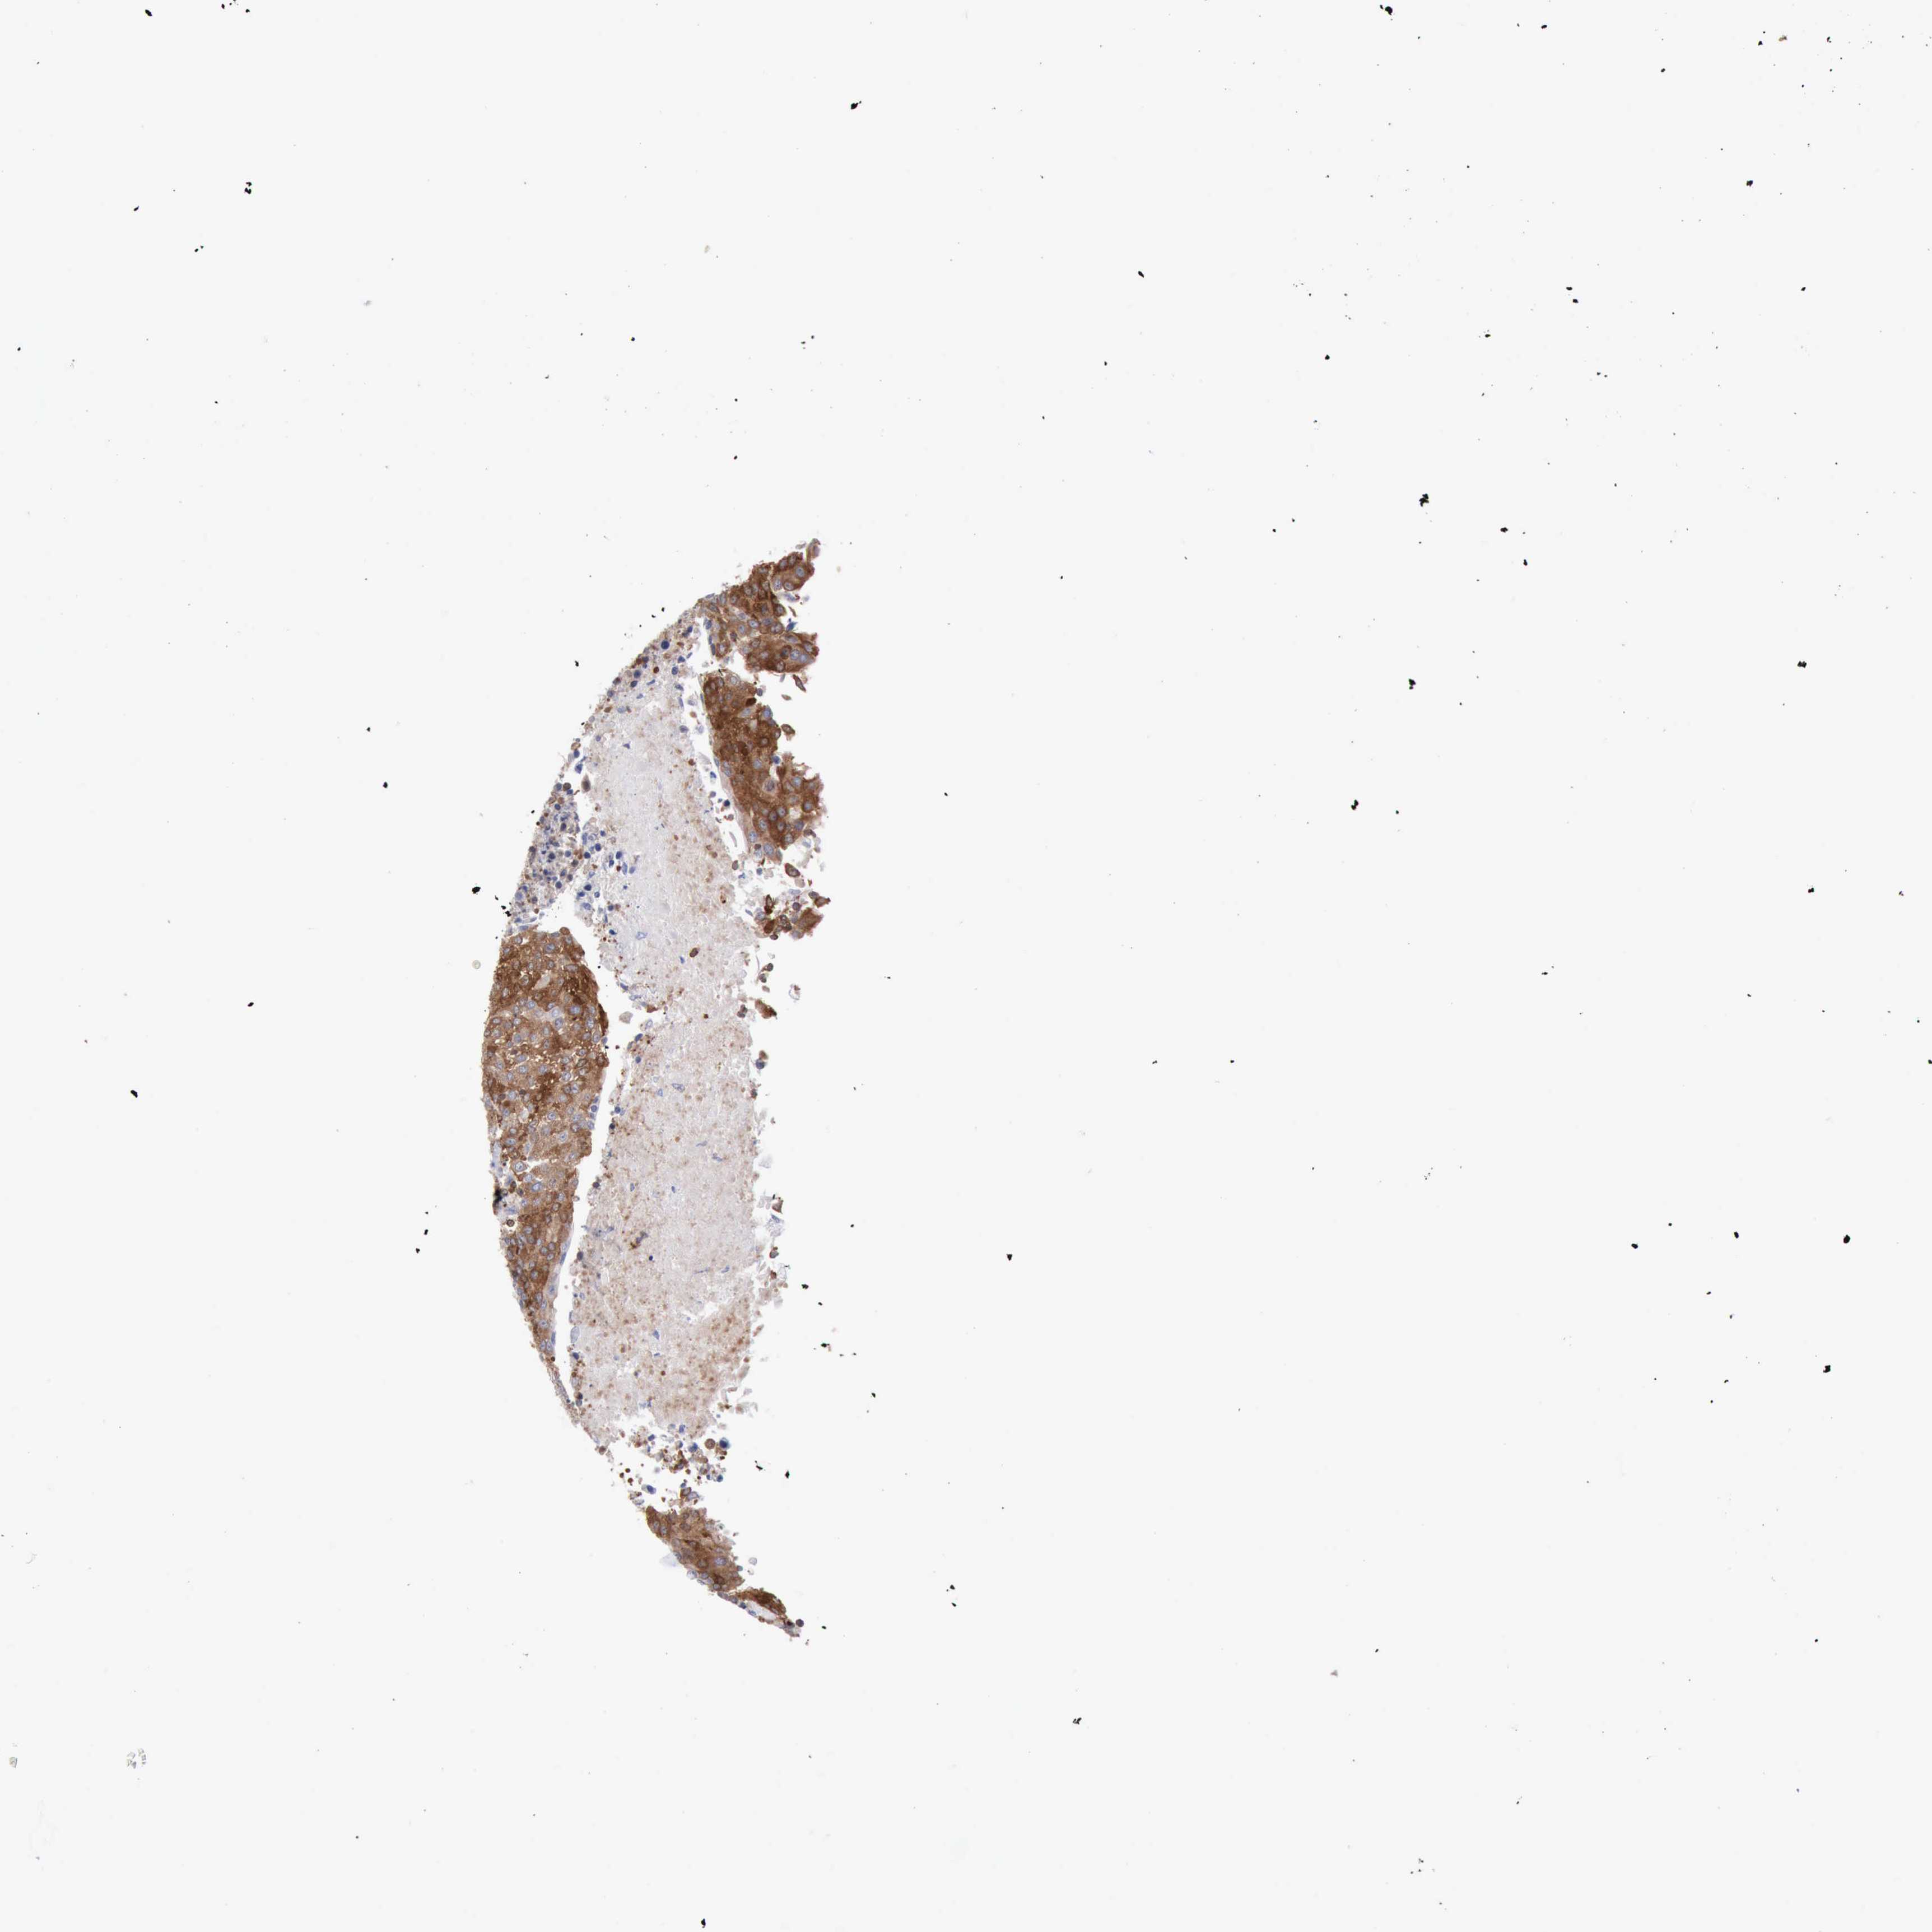

UROTHELIAL CANCER - Protein expressioni

A mouse-over function shows sample information and annotation data. Click on an image to view it in a full screen mode. Samples can be filtered based on level of antibody staining by selecting one or several of the following categories: high, medium, low and not detected. The assay and annotation is described here.

Note that samples used for immunohistochemistry by the Human Protein Atlas do not correspond to samples in the TCGA dataset.

Antibody stainingi

Antibody staining in the annotated cell types in the current human tissue is reported as not detected, low, medium, or high, based on conventional immunohistochemistry profiling in selected tissues. This score is based on the combination of the staining intensity and fraction of stained cells.

Each image is clickable and will lead to virtual microscopy that enables deeper exploration of all samples and also displays staining intensity scores, fraction scores and subcellular localization as well as patient and tissue information for each sample.

Antibody HPA001032

Antibody HPA027214

Antibody CAB037024

Urothelial carcinoma, High grade

Urothelial carcinoma, Low grade

Urothelial carcinoma, NOS